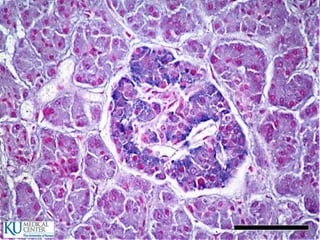

Glándulas salivales principales

 Glándula parótida

 Glándula submaxila

 Glándula sublingual